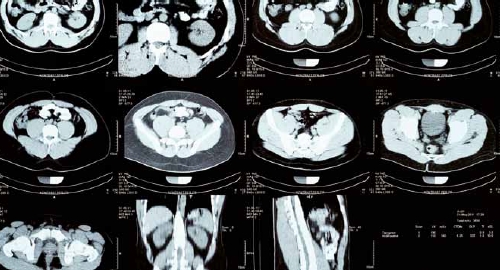

Una revolución completa en el mundo de la tomografía computarizada

La tecnología Photon Counting de Siemens Healthineers crea imágenes de tomografía computarizada (TC) de alta resolución espacial, sin ruido electrónico y con una relación contraste-ruido mejorada, información multiespectral intrínseca y a una dosis de radiación más baja, lo que permite obtener imágenes más detalladas con información anatómica y funcional para percibir patologías antes no identificadas.

En concreto, esta tecnología permite una mayor visualización de pequeñas estructuras anatómicas y, gracias a su aporte de información espectral intrínseca en cada escaneo, brinda información funcional que aporta mayor precisión diagnóstica. En otras palabras, se trata de una técnica poco invasiva que permite obtener un análisis minucioso de las imágenes obtenidas que ofrecen mayor seguridad y precisión. Así, los profesionales médicos pueden ofrecer diagnósticos concluyentes y tomar decisiones terapéuticas seguras.

Lo que ha hecho Siemens Healthineers es un cambio de paradigma, ya que ha modificado completamente la tecnología que se usa en el detector. Ahora mismo, NAEOTOM Alpha® con Quantum Technology® es el único equipo que hay comercialmente disponible de esta categoría de TC basada en medición o control de fotones, y se ha invertido en él cerca de 20 años de investigación.

Este escáner supone una revolución completa en el mundo de la tomografía computarizada. Este detector es capaz de leer cada uno de los fotones que le llega sin tener que transformarlo en luz como pasaba hasta ahora, leyendo más fotones, dándonos mucha más información e información mucho más precisa. Reduce la cantidad de pruebas, amplía el abanico de pacientes que pueden acceder a hacerse una TC, permite detectar patologías más precozmente o patologías que hasta ahora no se identificaban fácilmente.